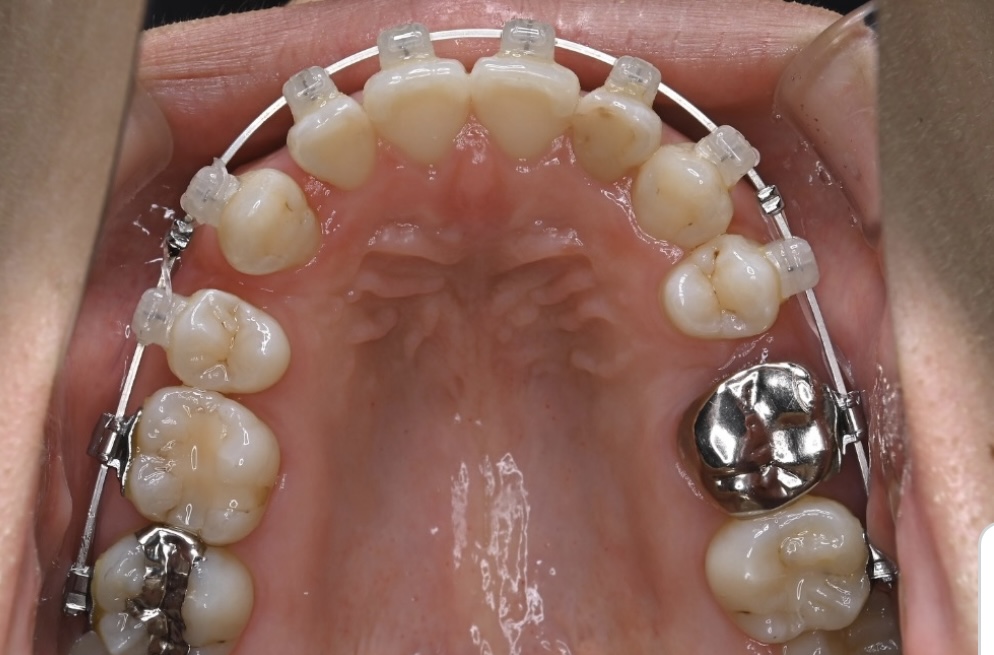

最初に来られた際の写真です。上の前歯が前側にありますが内側を向いており、前歯の噛み合わせが深い状態であり、ガタガタもあります。